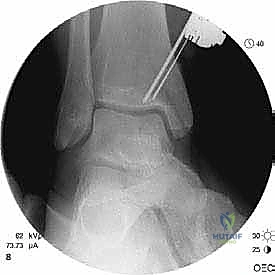

- التصوير بالأشعة السينية (X-rays): الخطوة الأولى لاستبعاد الكسور الكبيرة وتقييم المحاذاة العامة للعظام. قد تظهر الأشعة السينية الآفات الكبيرة، لكنها غالباً ما تفشل في إظهار التلف الغضروفي المبكر.

- التصوير المقطعي المحوسب (CT Scan): ضروري جداً للآفات الكبيرة. يوفر الـ CT صورة ثلاثية الأبعاد للعظم، مما يساعد الجراح في التخطيط الدقيق لعملية قطع العظم وحجم الطعم المطلوب زراعته.